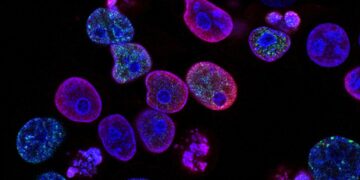

Read moreCancer Deaths Fall While New Diagnoses Climb Cancer-related deaths in the U.S. have seen a notable decline of 34% from...

Read moreCommon Diabetes Medication May Help Prevent Skin Cancer A recent study published in the Journal of Drugs in Dermatology found...